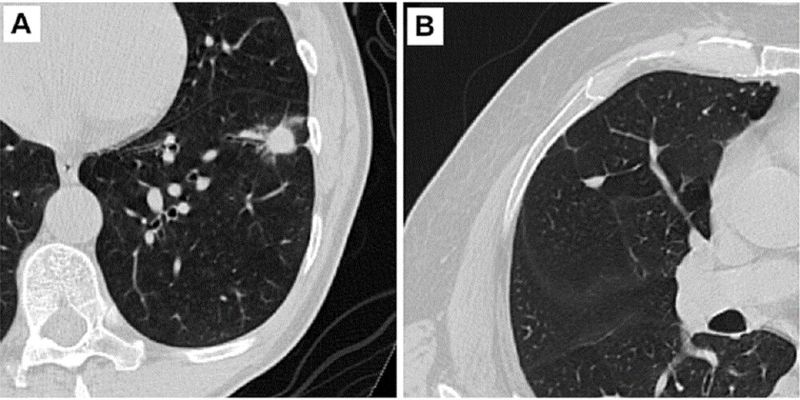

Predicting Cancer Risk in Lung Nodules with AI